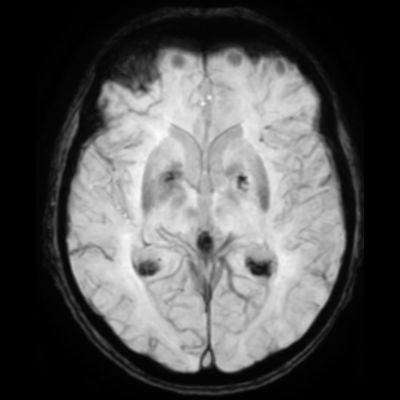

75 yaş, K

Sağ üst kolda atım şeklinde hareket

Tanınız nedir?

Nonketotik hiperglisemik hemikore

Diyabetik striatopati

Non-ketotik hiperglisemiye bağlı hemikore-hemibalizm

non-ketotic hyperglycemic hemichorea